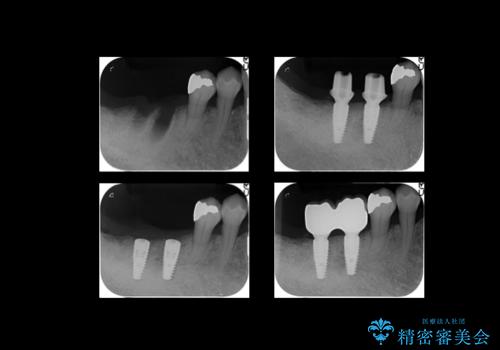

- 右下の奥歯が割れてしまい、抜歯を行いました。

ブリッジにできない位置であったため、インプラントでかめるようにしました。

また、向かい合う上の歯が挺出(伸び出してしまうこと)しており、インプラントを入れることが難しかったため、長さを短くかぶせ治しました。